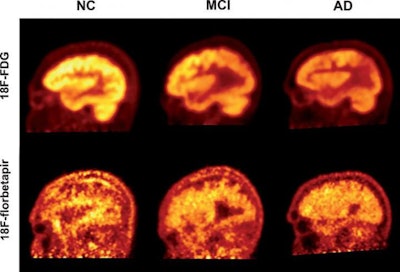

FDG-PET is superior to amyloid PET imaging with the radiopharmaceutical florbetapir for assessing cognitive decline in patients with Alzheimer's disease or mild cognitive impairment, according to research published in the August issue of the Journal of Alzheimer's Disease.

In a study that compared FDG-PET and florbetapir-PET in normal controls and patients with Alzheimer's disease and mild cognitive impairment, a team of researchers led by Dr. Abass Alavi, PhD, of the University of Pennsylvania and Dr. Andrew Newberg of Thomas Jefferson University in Philadelphia found that quantitative FDG-PET results had a much higher correlation with participant scores on the Mini-Mental Status Examination (MMSE).

Of the 63 participants in the study, 19 had clinically diagnosed Alzheimer's disease, and 23 had mild cognitive impairment; the remaining 21 subjects were healthy controls. All subjects received a brain CT scan followed by a PET scan -- initially with FDG and then with florbetapir.

The researchers then performed global quantitative analysis of the supratentorial region to produce a global standardized uptake value (SUV), which was calculated as a weighted average of the mean SUVs from five cerebral regions. Although the researchers found that both FDG-PET and florbetapir-PET could effectively discriminate individuals with dementia from the healthy control group, they concluded that FDG-PET had a much higher correlation with low cognitive performance.